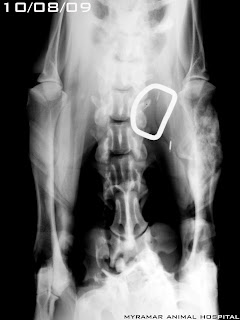

Venom, Boxer de 18 meses llega a consulta con cojera evidente del miembro anterior izqdo. Tras examen radiológico y estudio histopatológico se diagnostica osteosarcoma primario de húmero.

Se muestra el estudio radiológico.